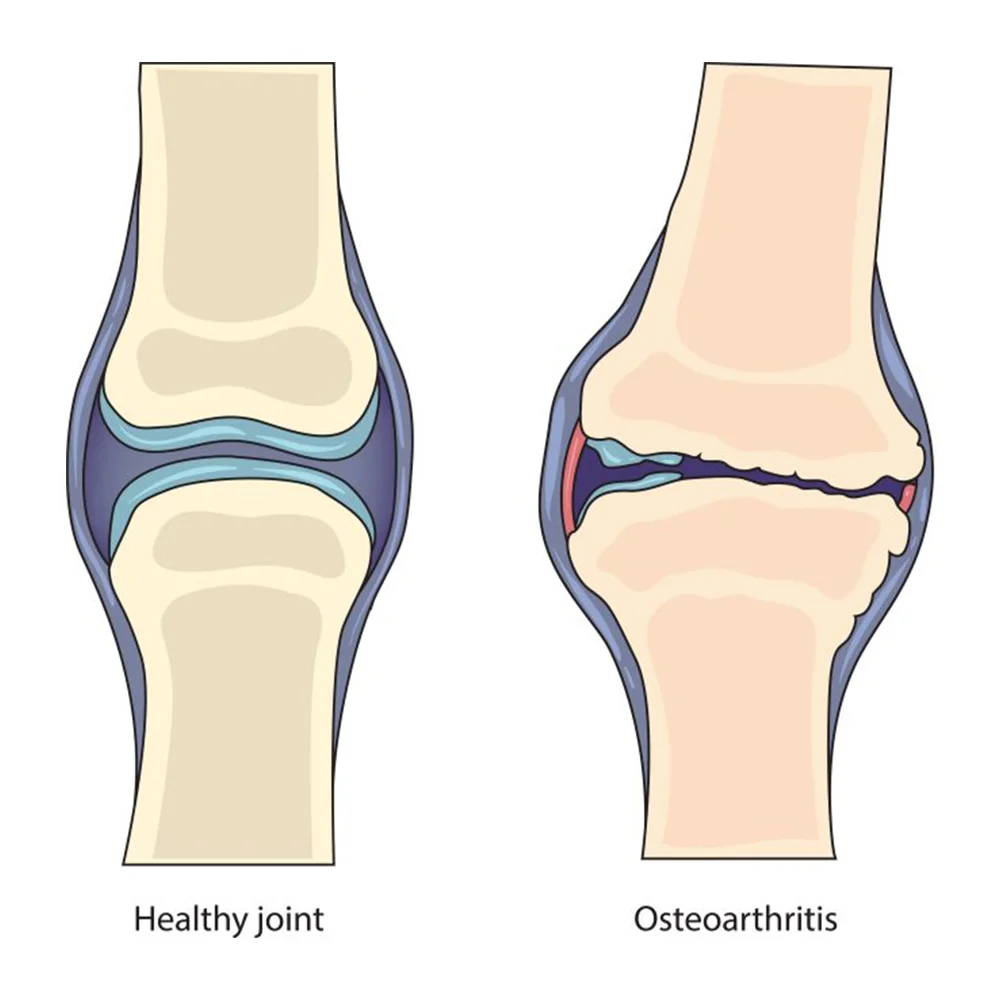

Joint Pain – Osteoarthritis

Joint pain happens when the cartilage wears down and the joint gap reduces, a condition called osteoarthritis. It can affect knees, hands, hips, or other joints, causing stiffness, swelling, and difficulty in movement. With Woonac, you can naturally reduce joint pain and improve flexibility.